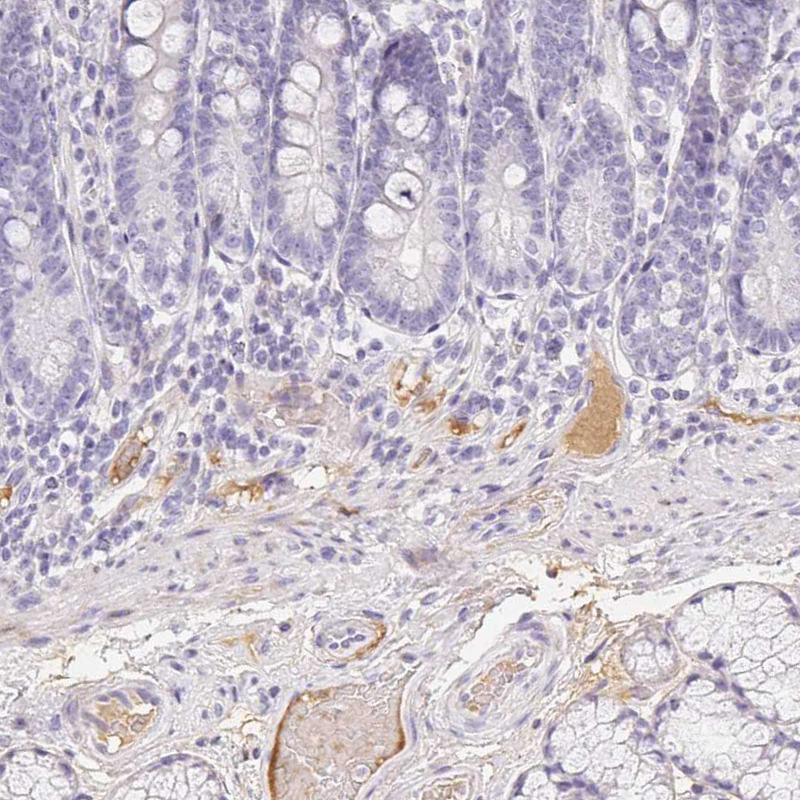

Immunohistochemical staining of human duodenum shows moderate positivity in plasma in blood vessels.